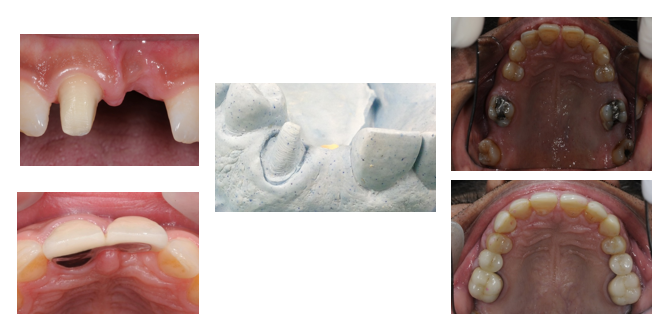

What is a pontic?

Pontic: An artificial tooth on a fixed dental prosthesis that replaces a missing natural tooth, restores its function, and usually fills the space previously occupied by the clinical crown

What is an ovate pontic?

A pontic design requiring soft tissue surgery, mostly used for anterior teeth.

What is a modified ridge lap pontic?

A pontic design that is the most common type.

contact with ridge buccaly